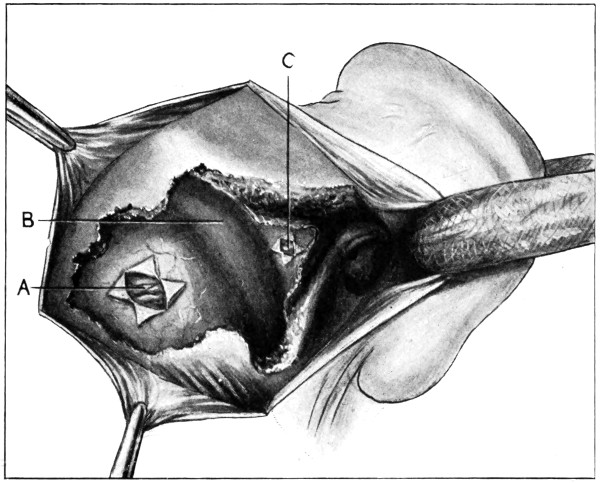

Fig. 19. Third Stage in the Formation of an Osteoplastic Flap. The dural flap turned down and the brain exposed. Note the relation of the scalp, bone, and dural incisions to one another.

Reference has already been made to the great importance of opening the dura in such a manner as to avoid injury to the underlying superficial cerebral vessels (see p. 19). It may be incised in a crucial manner or by flap-formation. Flaps are usually to be preferred if the surgeon desires to have the widest possible view of the brain surface. In the formation of the flap, advantage should be taken of the vessels that minister to its vitality. Thus, in the lateral region of the head, the base lies below, the middle meningeal artery supplying the flap. Under special circumstances, the blood-supply may be disregarded; the flap never sloughs, so far as my experience goes.

Considerable difficulty may be experienced in sewing up the dura—by reason of the bulging of the brain. How these difficulties may be overcome is dealt with on p. 236. The edges should be united by numerous fine silk sutures.